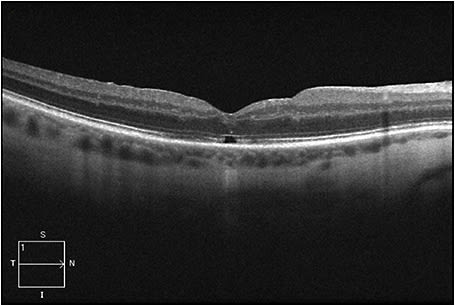

Figure 4 (page 50) shows FTMH closure one month following PPV, with a VA of 20/30 at this time. Figure 5 (page 50) shows the same eye almost one year following PPV: the FTMH remained closed with mild attenuation of the subfoveal ellipsoid zone, and the vision remained stable.

Figure 4. FTMH closure is seen one month following PPV, with a VA of 20/30 at this time.